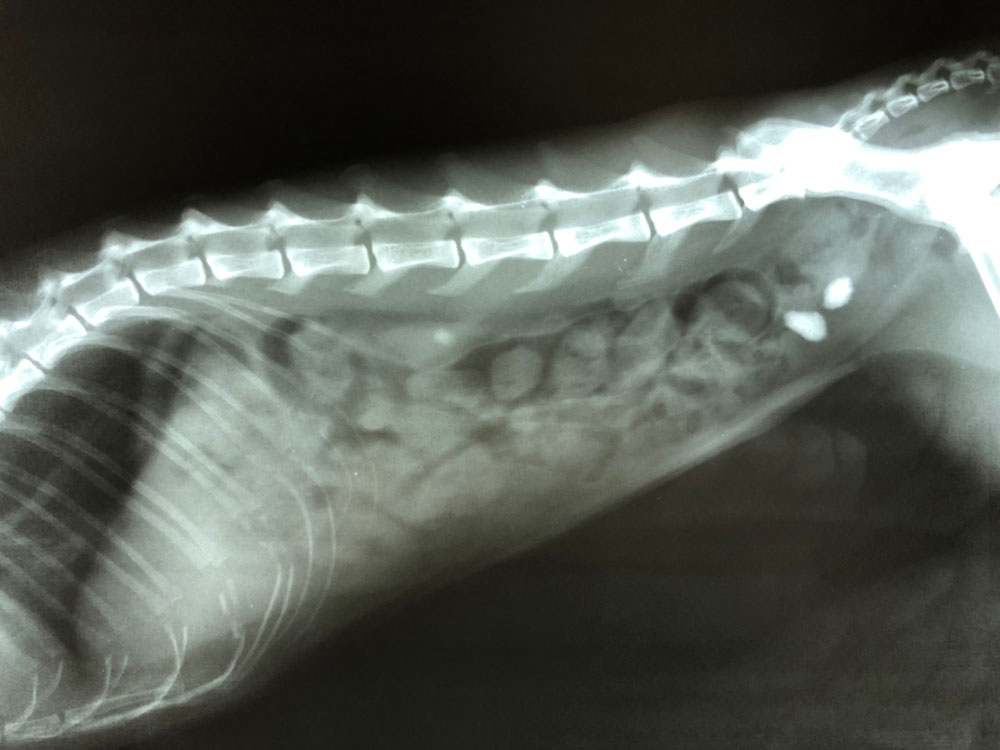

요로결석 치료방법

요로결석에 대한 치료의 선택은 돌의 크기, 위치, 구성 및 증상의 심각성을 포함한 몇 가지 요인에 따라 달라집니다. 일반적인 치료 방법은 다음과 같습니다.

체외충격파쇄석술 (ESWL): ESWL은 인체의 외부 충격파를 사용하여 더 큰 돌을 요로를 쉽게 통과할 수 있는 더 작은 조각으로 분해하여 자연배출을 유도하는 비수술적인 치료 방법입니다. 이 시술은 신장이나 요관에 있는 결석에 사용되는 경우가 많습니다.